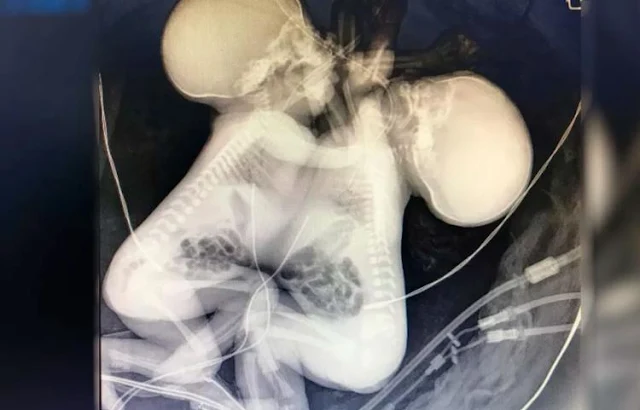

As gêmeas siamesas

baianas que nasceram, na última quinta-feira, 26, unidas pelo tórax e

compartilhando o coração morreram na tarde desta quarta, 2, em Goiânia. A mãe

das crianças foi encaminhada de Salvador para Goiânia por causa da complexidade

do parto.

De acordo com

informações do G1 Goiânia, as meninas estavam internadas no Hospital Estadual

Materno Infantil Jurandir Nascimento (HMI). A causa da morte foi devido à má

formação cardíaca. As gêmeas nasceram

com 34 semanas de gestação e pesaram 3.044 kg.

O HMI informou que o

velório será na cidade da família. Segundo a equipe médica, a cirurgia de

separação seria impossível, já que as gêmeas nasceram com os corações colados,

músculo com músculo.

Foto: Zacharias Calil / A TARDE